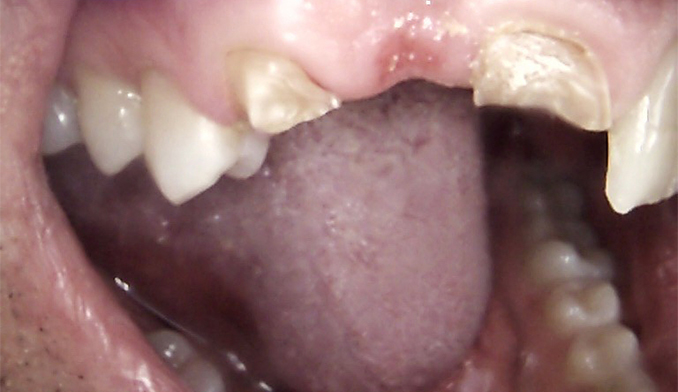

Same-Day Crown for Broken Molar

The patient broke a lower molar (second tooth from the back) while eating. Fortunately, the tooth was salvageable. We completed a same-day crown within two hours, restoring full strength and function.